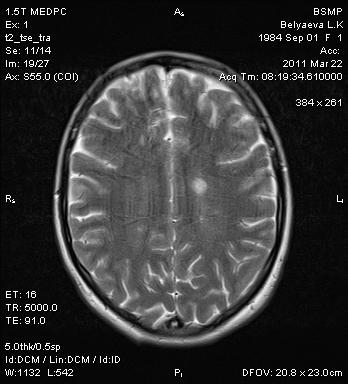

Молодая девушка, несколько дней назад произошло выпадение чувствительности на руках. Начало заболевания острое. В анамнезе операция (3 года назад) на почке по поводу аденокарциномы - секторальная резекция, почка сохранена. Ваще мнение коллеги??

Пациентка изначально была направлена на исследование грудного отдела. Выложены только отдельные срезы (выкладываю первый раз - на DICOM-сервер пока не разобрался как загрузить). От контрастирования пациентка отказалась.